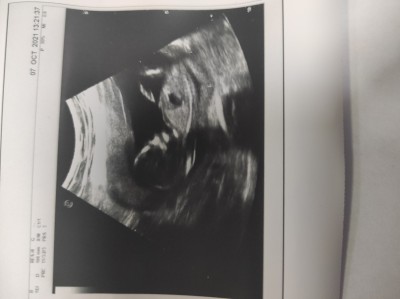

Kizlar merhaba buraya ilk defa yazıyorum çok heyecanlıyım cinsiyet tahmininiz var mı acaba

Gebelik haftası 14

Bacak arası sanki boş gibi kız diyorum ben :) gönlüne göre olsun

Kiz gibi duruyo hayırlısı olsun.